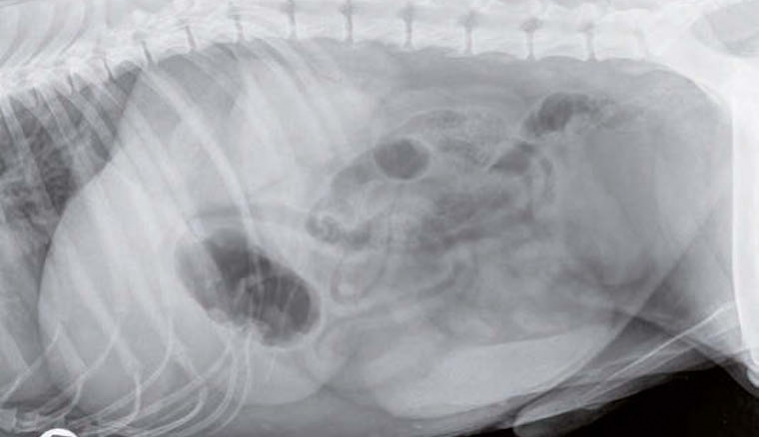

Radiographie abdominale de profil d'un chien souffrant de pancréatite aiguë : perte de contraste dans l'abdomen crânial droit, présence de gaz dans le duodénum.

© Université de Gand.